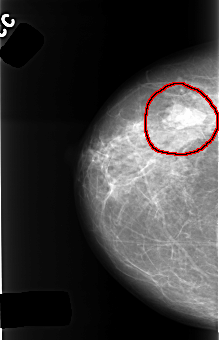

C_0415_1.RIGHT_MLO

FILE: C_0415_1.RIGHT_MLO.OVERLAY

TOTAL_ABNORMALITIES 1

ABNORMALITY 1

LESION_TYPE MASS SHAPE LOBULATED MARGINS CIRCUMSCRIBED

ASSESSMENT 4

SUBTLETY 5

PATHOLOGY BENIGN

TOTAL_OUTLINES 1

BOUNDARY